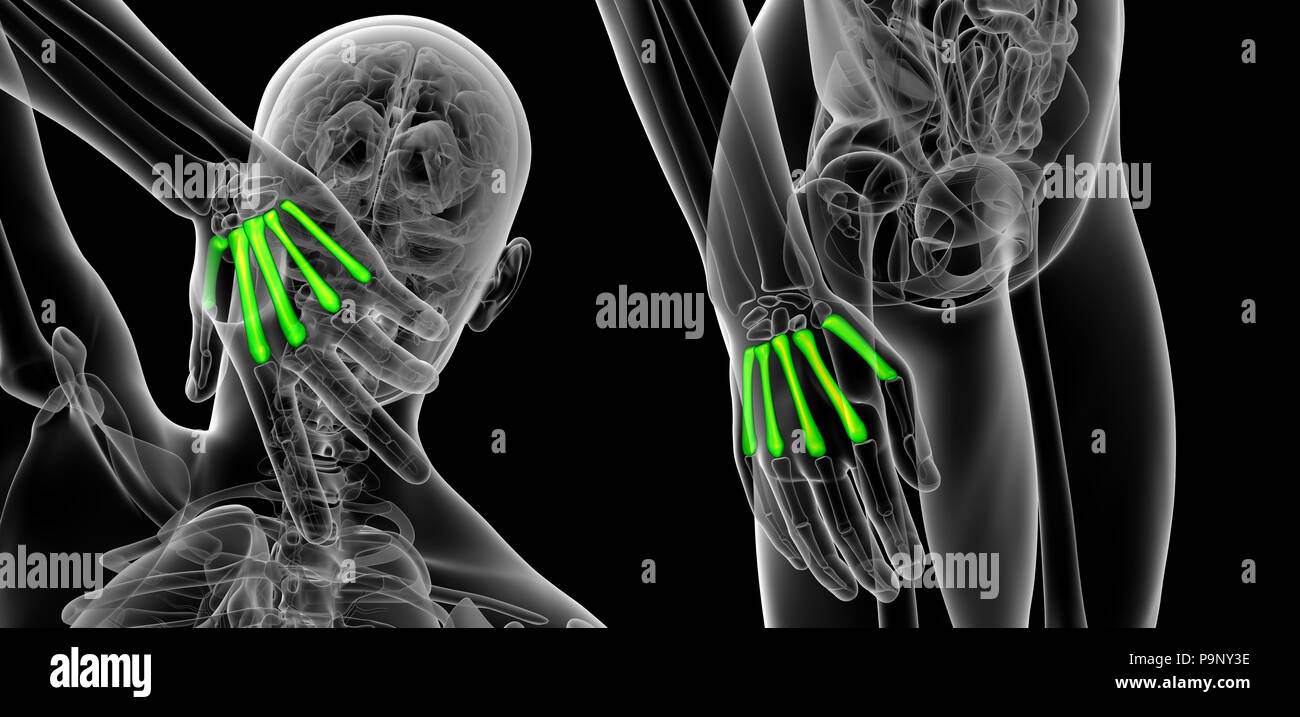

3d rendering illustration of metacarpal Stock Photohttps://www.alamy.com/image-license-details/?v=1https://www.alamy.com/3d-rendering-illustration-of-metacarpal-image212538578.html

3d rendering illustration of metacarpal Stock Photohttps://www.alamy.com/image-license-details/?v=1https://www.alamy.com/3d-rendering-illustration-of-metacarpal-image212538578.htmlRFP9NY3E–3d rendering illustration of metacarpal

3d rendering of metacarpal Stock Photohttps://www.alamy.com/image-license-details/?v=1https://www.alamy.com/3d-rendering-of-metacarpal-image212538382.html

3d rendering of metacarpal Stock Photohttps://www.alamy.com/image-license-details/?v=1https://www.alamy.com/3d-rendering-of-metacarpal-image212538382.htmlRFP9NXTE–3d rendering of metacarpal